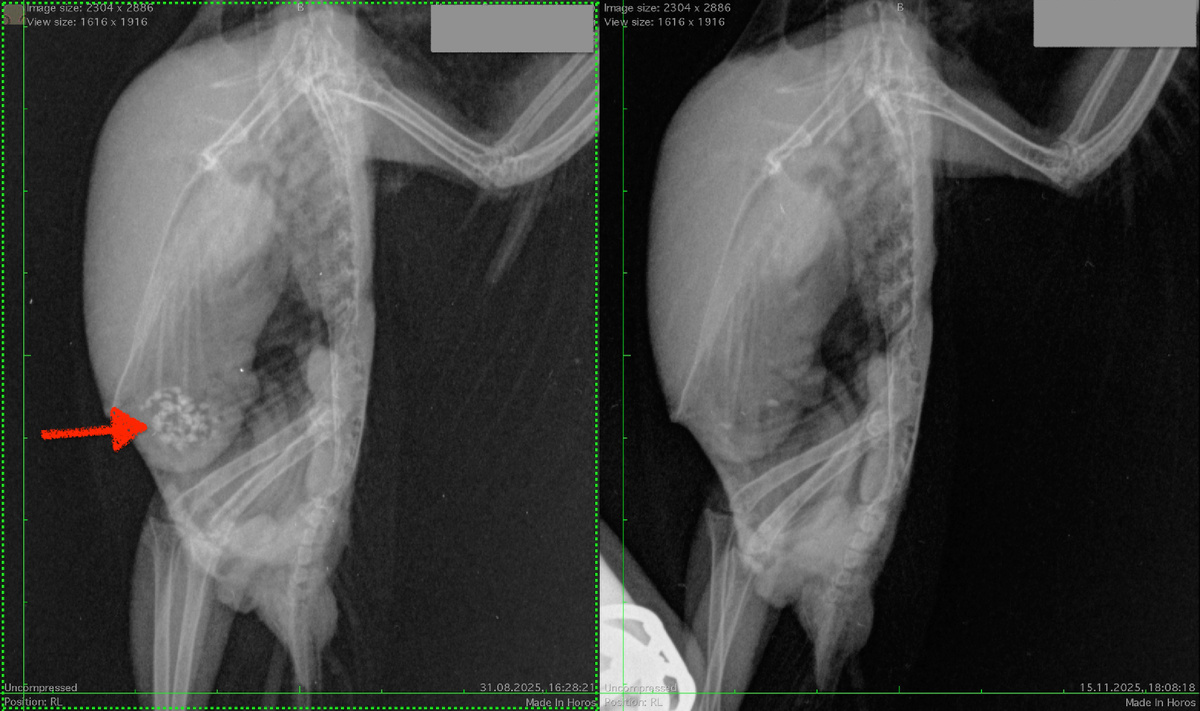

Вот пример из моей практики. Две пирруры, с последствиями птенцового рахита (выкормыши) и комплексом бактериально-грибковых инфекций. Обследованы почти сразу после покупки (это снимки с левой стороны). Помимо множества проблем у обеих птиц мускульные желудки (показаны стрелкой), содержат много гравия и инородного материала, а железистые желудки содержат просто много мягкого инородного материала. У этих птиц очень сильный болевой синдром.

рентген больного попугая до и после лечения. Стрелкой обозначено скопление песка в желудке.

С правой стороны снимки этих же птиц через 2.5 месяца лечения антибиотиками, обезболивающими и прочими препаратами. От грибковой инфекции лечение пока не начинали (идёт подготовка к лечению от "аспергиллёза"). Гравий у птиц в свободном доступе, но после начала обезболивания птицы перестали им интересоваться. У обеих птиц песка в мускульном желудке практически не осталось, и железистые желудки уменьшились в объёме. Болевой синдром у птиц значительно меньше чем был.